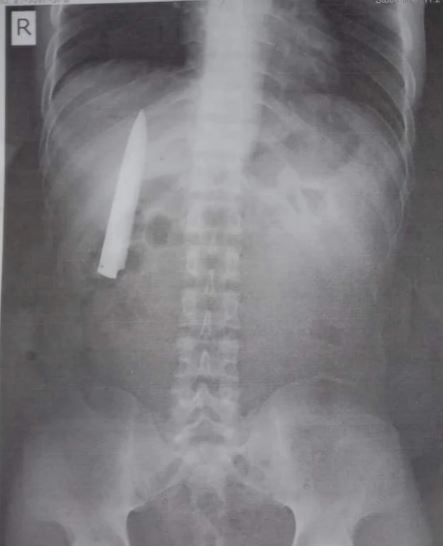

Seorang lelaki Filipina yang sering mengalami sakit pada dada khasnya ketika cuaca sejuk, tidak menyangka menemui sebilah pisau sepanjang empat inci yang tersangkut pada dadanya selepas melakukan imbasan X-ray.

Kent Ryan Tomao, 25, bingung ketika doktor memberitahunya bahawa terdapat "objek menyerupai pisau" yang tersangkut di dadanya, sangat dekat dengan salah satu paru-parunya selepas ujian X-ray.

Ryan yang bekerja di lombong dekat Agusan del Sur tidak pernah membayangkan ada objek berkenaan dalam badannya yang membuatkannya sering sakit pada dada.

"Saya selalu tertanya-tanya mengapa saya merasakan sakit di dada ketika cuaca sejuk. Tetapi saya tidak sangka rupanya ada pisau dalam dada saya,” kata Ryan kepada sebuah stesen radio tempatan.

Ketika ditanya apakah dia tahu bagaimana pisau itu boleh berada dalam dada, beliau memberitahu doktor bahawa dia telah menjadi mangsa tikaman sejak setahun yang lalu. Suatu hari ketika sedang menunggang motosikal, dia diserang dan ditikam oleh sekumpulan pemuda. Tidak banyak yang dia ingat tentang kejadian itu, kecuali ketika dia hampir tidak bernyawa ketika dibawa ke hospital, namun akhirnya doktor berjaya menyelamatkannya.

Ketika itu beliau menganggap bahawa doktor sudahpun melakukan semua ujian yang diperlukan sebelum beliau dibenarkan keluar dari hospital, dan dia pasti tidak pernah membayangkan mereka meninggalkan pisau dalam dadanya.

Walaupun terkejut dengan penemuan pisau itu, beliau tidak mempunyai rancangan untuk mengenakan saman kepada doktor yang pernah merawatnya dahulu. Apa yang dia mahukan sekarang adalah mengeluarkan pisau dari dalam dadanya itu agar dia dapat meneruskan pekerjaan seperti biasa.